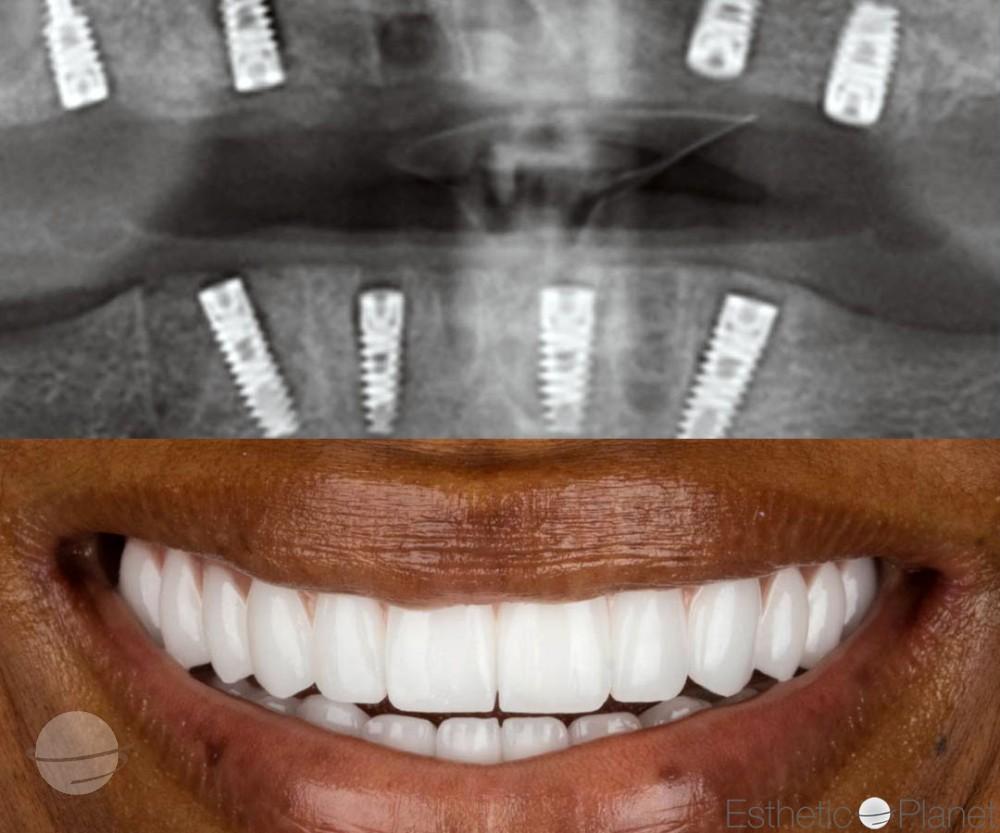

Résultats Avant / Après

Découvrez les transformations de nos patients